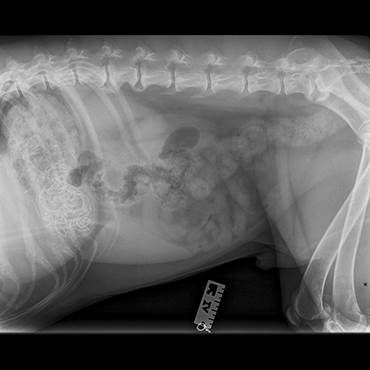

X-rays confirmed the tinsel was in Dexter’s stomach, but thankfully it hadn’t moved through to his intestines, which can cause additional complications. Kate Milroy, Vet Team Leader at PDSA Margate Pet Clinic, said: “Dexter needed to be taken straight in for emergency surgery, it was clearly causing a blockage and would be fatal for Dexter if we didn’t remove it as soon as possible. There’s always some risk with any kind of operation, but thanks to Dexter’s owner noticing the early signs of problems we were hopeful it would be straightforward. I was very surprised when I managed to pull the tinsel out all in one piece though!”